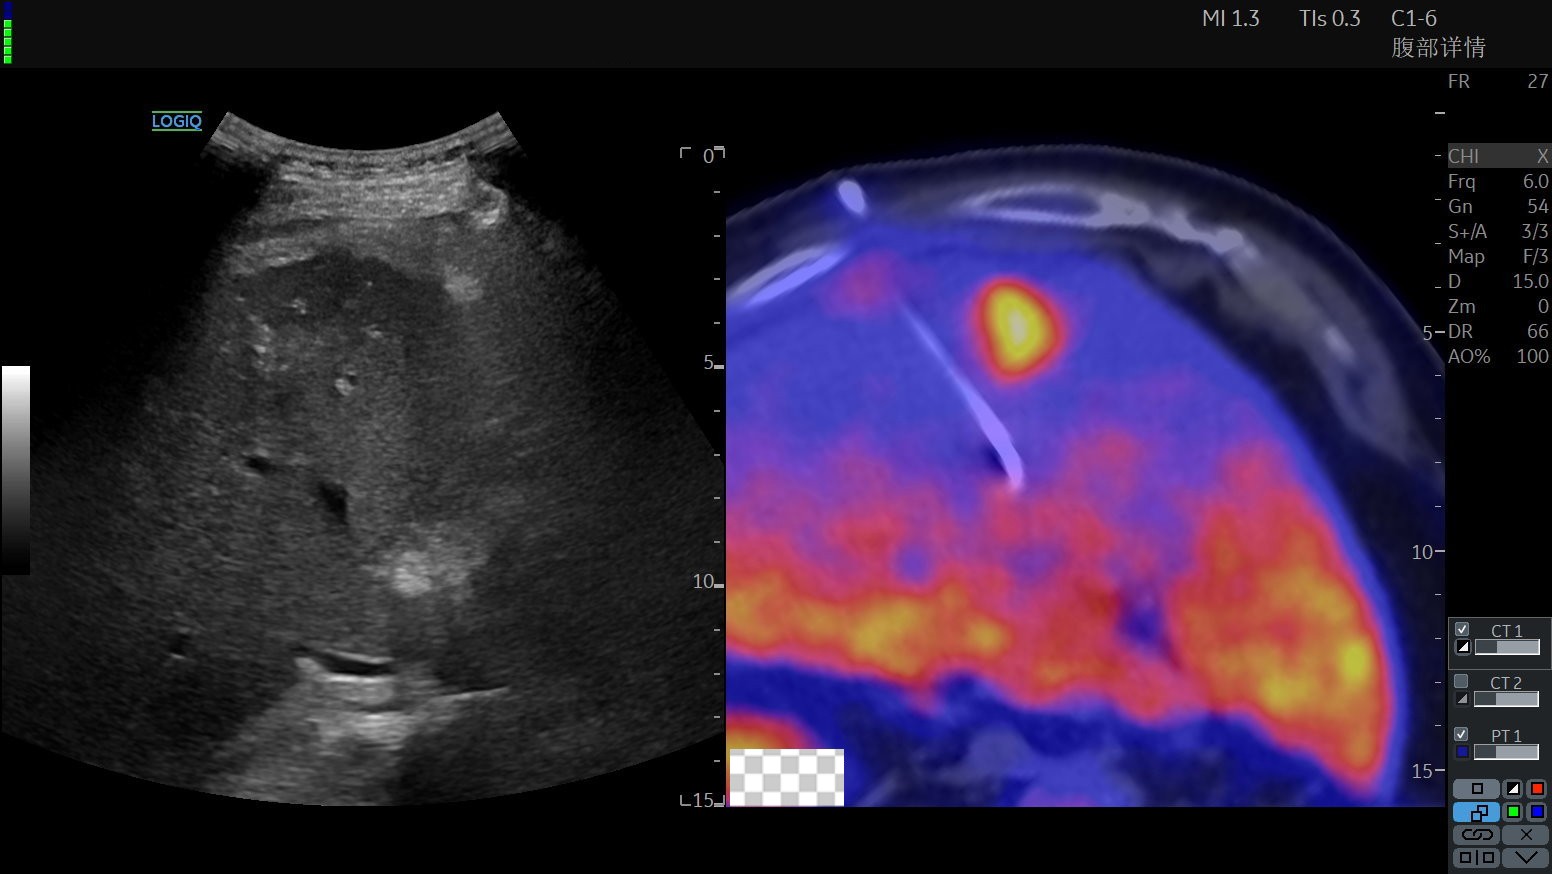

肿瘤医院超声介入科施行超声融合PET-CT引导下穿刺活检,整个过程仅需10-15分钟,既精准,又安全有效率。

24a01d4b30dcafc8e7006b4cc99ecd9b.jpg892159a573ee7ec2594f5d59d4e43265.jpg

超声介入专科医生术前配准、融合超声和PET-CT影像

超声设备显示的超声融合PET-CT图像,可以看到PET-CT精准显示高代谢肿瘤病变,配准融合后发挥超声影像的实时便捷性,再结合PET-CT影像清晰显示的高代谢靶目标